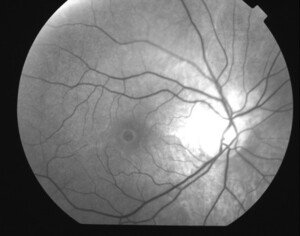

Figura 2. Imágen aneritra con agujero macular patente y control con foto color con agujero cerrado.